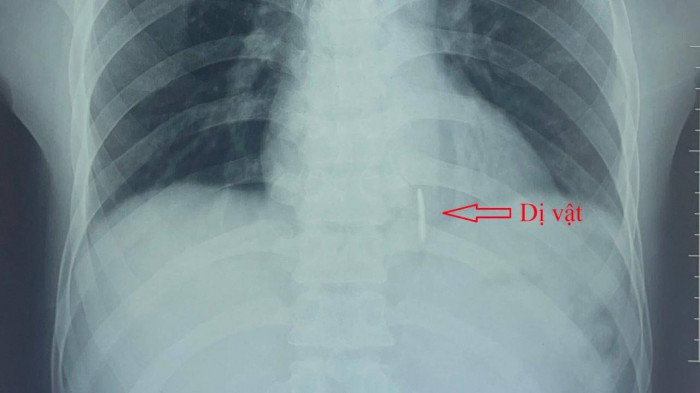

Kết quả chụp Xquang ngực tim phổi thẳng, siêu âm tim màu, chụp cắt lớp vi tính lồng ngực có cản quang ghi nhận có 1 dị vật cản quang dài 4 x 0,4cm nằm dọc thành sau thất trái và có thông vào buồng tim.

Hình ảnh dị vật trên phim Xquang tim phổi.